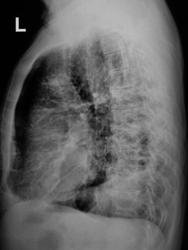

Пациент не проходил «флюшку» с 2007 года. Сегодня направлен на рентгенографию ОГК с подозрением на наличие хронического бронхита.

Уж больно тут много всего и пневмосклероз с эмфиземой и выраженной лёгочной гипертензией, и очаговые тени различной плотности, и органы средостения смещены влево  (хотя слева выраженные плевральные шварты и, вероятно, плевро-перикардиальные сращения). Справа в нижнем лёгочном поле какая-то кольцевидная тень (фиброз?, бронхоэктазы?). В такой ситуации лучше всего конечно раздобыть архив. Ну и конечно сделать томограммы, что бы убедиться что смещение средостения связано со спайками, а не с ателектазом нижней доли, а потом уже разобрать с очагами

То есть от флюшки только описание? К сожалению на томограммах не видно бронхов. А вот в проекции сердца какие участки просветления, возможно это бронхоэктазы в S10. А в остальном, наверно, очаги фиброза различной величины и формы, слева массивные плевро-апикальные и плевральные наложения ну и то, что писал раньше.

В мокроте (метод микроскопии) обнаружены "палки".

Все! Пациент отвезен в "областную туберкулёзную контору", фтизиатры признали в нем нечто родное и близкое...